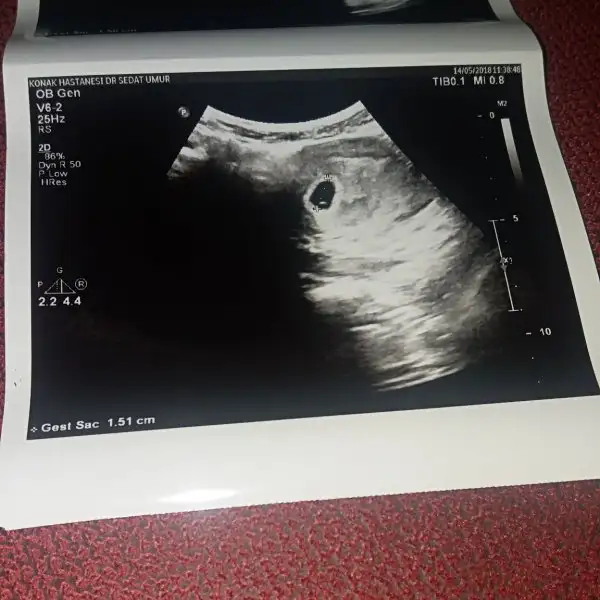

HADI GÖZUN AYDIN DARISI BIZEkızlarr bana ceza vermıslerr ben de mecbur gırdım tekrar baska hesapla bugun bebişimizi gördükk kese bebiş ve yolc sac goründüü :)Eki Görüntüle 2146352

kızlarr bana ceza vermıslerr ben de mecbur gırdım tekrar baska hesapla bugun bebişimizi gördükk kese bebiş ve yolc sac goründüü :)Eki Görüntüle 2146352 masallah annesi bak mini minnacik daha darisi bana ins yarina rabbim kismet ederse

Ayy cokk sevindim insallah darisi basimiza yaçokk sağolunn saglıkla görunn canlar hem de nasıl güzel karsımda da ekran vardı bı görduk Allahım eşim bıle aglıcaktı 3hafta sonra kalp atışı dedı benım dr.um bıraz garantıcı adet günü 12gun snra gel dedı dıye uzulmustum ama smdı bebişi de gördük ılk gidişte oyuzden 3hafta gecer ınsallah bıaonce kalbı de duyarız:)

Benimde 5 ocak bugun gittim kese 14 mm olmuştu doktor haftaya tekrar çağırdı umarım herşey yolunda gidiyordur. Seninde gözün aydın7 ocak canm

Geceden beri agrım vardı kızlar eşim dayanamadı hastaneye getirdi yaklaşık 1cm sağ tarafta kist varmış o ağrı yapmış kesemizide görmüş olduk oda 6mm mis inşallah sıkıntı olmaz